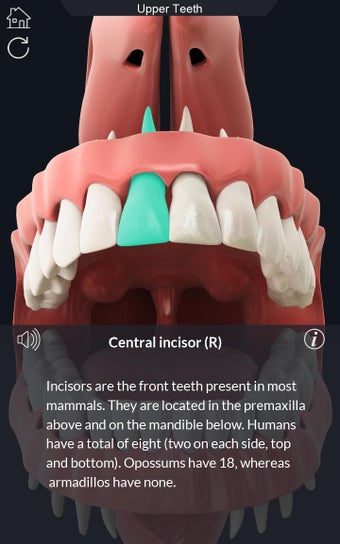

Uygulama, diş hekimliği ve anatomisi öğrencileri ve öğretmenleri için olmazsa olmaz bir araçtır. Hem öğrenciler hem de öğretmenler için bir eğitim aracı olarak kullanılabilir. İnsan dişlerini yüksek kaliteli grafiklerle keşfetmenizi sağlar. Ayrıca insan dişlerine derinlemesine bir bakış sunar.

Uygulama, her bir parçayı seçerek adını görüntülemenize veya ilgili bilgileri okumanıza olanak tanır. Her bir parçayı gizlemeyi veya göstermeyi seçebilirsiniz. Ayrıca 360° döndürebilir veya yakınlaştırıp uzaklaştırabilirsiniz. Kamerayı modelin farklı bir görünümünü elde etmek için hareket ettirebilirsiniz.